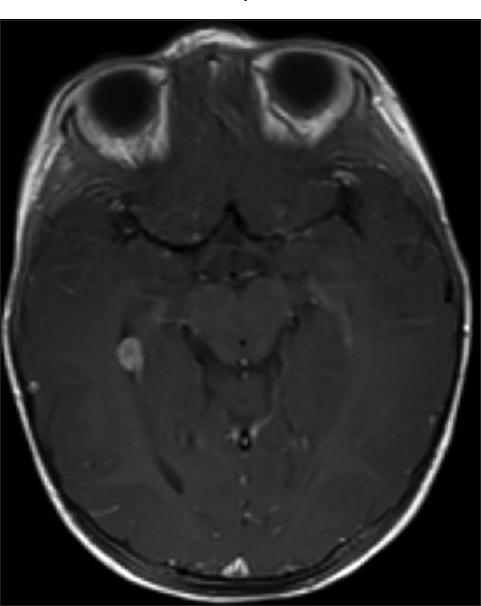

Choroid plexus tumors (CPT) in the pediatric population are usually discovered in symptomatic patients often with symptoms of increased intracranial pressure, with hydrocephalus as the most common presentation, along with seizures, subarachnoid hemorrhage, or focal neurological deficit. Most CPTs are found to be benign choroid plexus papillomas (CPP), whereas a small number are intermediate and malignant choroid plexus carcinomas (CPC). Total surgical resection is the established definitive treatment for symptomatic CPP.

We describe a young female who was found to have an incidental CPT during workup for recent head trauma without neurological deficits or hydrocephalus. She underwent a surgical operation to remove the tumor successful, with 1-year follow-up showing no recurrence and normal developmental milestones.